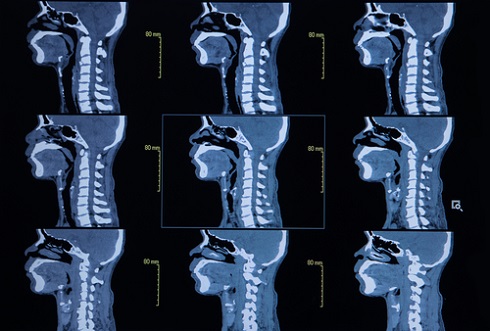

Прежде всего компьютерная томография органов и мягких тканей шеи применяется в онкологии и хирургии, реже — в других областях. Это обследование основывается на использовании рентгеновского излучения, которое направляется на определенную область для ее сканирования и получения изображения. В случае с шеей КТ-диагностика занимается исследованием щитовидной железы, гортани, пищевода, носоглотки, а также сосудов, мышц шеи, лимфатических узлов и трахеи.

Показаниями к проведению компьютерной томографии являются: патологии в области шеи, аномальное развитие органов, подозрение на злокачественные или доброкачественные опухоли, травмы, кисты, дивертикулы, заболевания пролегающих в шее кровеносных сосудов, воспаления лимфоузлов и прочие болезни находящихся здесь органов. Компьютерная томография нередко становится дополнительным исследованием, на которое направляют для уточнения результатов других видов диагностики.